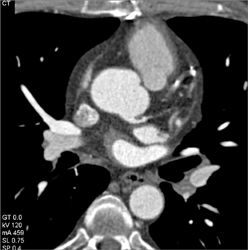

Patent Bypass Grafts But Plaque Distally-see Full Sequence